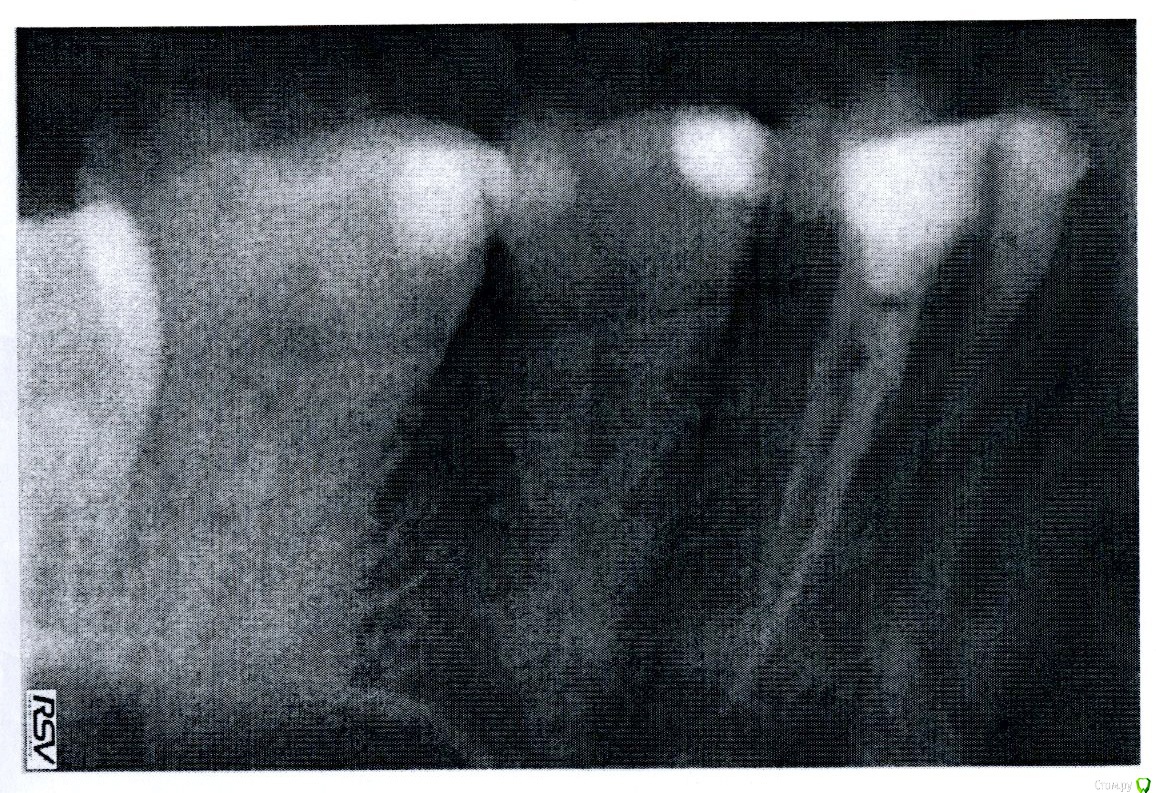

Taste of Honey Опубликовано 20 мая, 2015 Автор Поделиться Опубликовано 20 мая, 2015 (изменено) Пошла в клинику, сделали рентген. Прошу прощения, но качество, кажется, ужасное: делала бабуля, у которой кое-что получилось только на 6-й раз (это ж какую дозу я получила?!..). Потом она распечатала и дала мне... 2 листочка. Я попросила пленку или записать на флешку - оказалось, ни того, ни другого они не могут мне предложить, т.к. пленки нет (аппарат не фурычит), на флешку тоже почему-то нельзя. А еще раз облучаться страшно...Может быть, можно что-нибудь здесь разобрать? Зуб с пломбированным каналом.P.S. Зуб реагирует (несильно) при полоскании тепло-горячей жидкостью. Самопроизвольно не болит.Спасибо! Изменено 20 мая, 2015 пользователем Taste of Honey Ссылка на комментарий